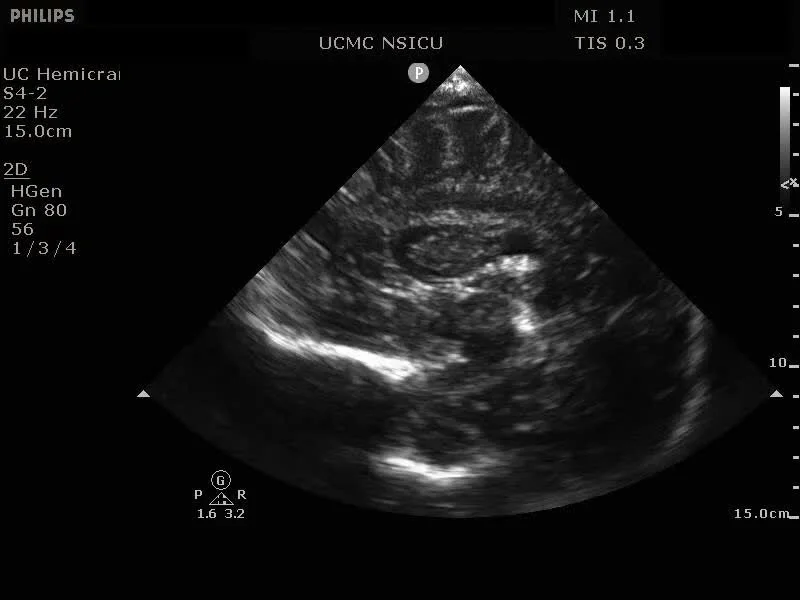

CRUSH: Cranial Ultrasound Via Hemicraniectomy

AKA Hemicraniectomy Ultrasound: Point of Care Ultrasonography (HOCUS POCUS)

Video 1: Axial view demonstrating the midbrain, collicular plate, and falx